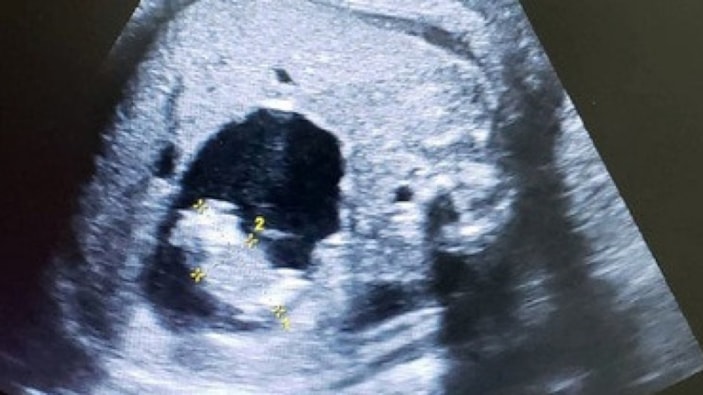

Doktorlar, doğmamış bebeğin ultrasonunda ilginç bir görüntüyle karşılaştı.

Ultrasonda, dünyaya gelmemiş bebeğin karnında, iki fetüs daha bulunduğu gözlemlendi.

Başlangıçta normal seyreden hamilelikte önceki taramalarda herhangi bir sorun görülmedi. Ancak son kontrolde fetüsün karnında kemik içeren anormal bir yapı fark edildi.

Yapılan testler, bebeğin karnında gelişimini tamamlayamayan iki hatalı fetüs bulunduğunu ortaya koydu.

Taramayı yapan Dr. Prasad Agarwal, "Bebeğin karnında kemik içeren fetüs benzeri bir yapı tespit ettik. Bunun çok nadir görülen bir 'fetus in fetu' vakası olduğunu anladık" dedi.